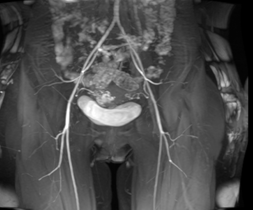

磁共振成像(MRI)能清晰显示子宫及其周围组织的解剖结构,有助于评估异常血管的走行、范围及其与邻近器官的关系,为临床诊断与治疗规划提供重要依据。

(子宫动静脉瘘MRI影像示意图)

典型MRI表现包括:

■ 子宫动静脉瘘MR-T1WI和T2WI序列子宫肌层或宫旁组织中可见卷曲扩张的流空信号,表现为无信号或低信号区域,类似血管的“流空效应”,提示存在异常扩张的血管团;

■ 增强T1WI序列病变部位可见迂曲的血管强化影,显示粗大的动脉血管与引流静脉直接交通,且无连接两者的毛细血管网;

■ 部分患者伴随子宫体积增大,子宫肌层交界区可能破坏,出现锯齿状或不规则的血流相关信号,提示病变累及肌层;

■ MRI可清晰显示动静脉瘘与周围组织(如宫旁血管、膀胱、直肠等)的关系,帮助评估病变范围及是否侵犯邻近器官。